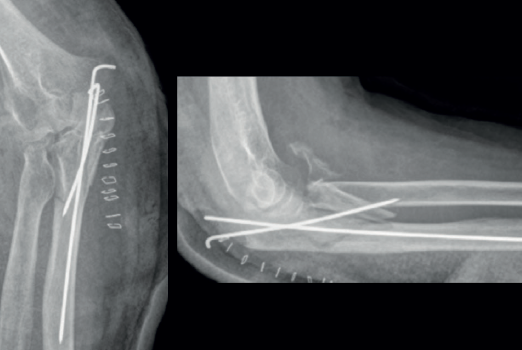

Las placas colocadas en la superficie posterior del cúbito son el sistema de fijación recomendado, proporcionando una fijación más resistente que los cerclajes con agujas de Kirschner y además permiten la fijación adicional de los fragmentos óseos y de la coronoides con tornillos o placas ortogonales en las superficies medial o lateral en los casos con gran conminución metafisaria(1,2,17). Las placas especialmente diseñadas de olécranon (Figuras 5 y 6) o las placas de compresión dinámica de contacto limitado (LC-DCP) de 3,5 mm conformadas para adaptarse a la morfología del cúbito son preferibles a las placas semitubulares, al aportar una fijación más estable(2,18,19).

Cuando la fractura del olécranon incluye una fractura de la coronoides, la reducción y la fijación de esta es condición imperativa para conseguir la estabilidad humerocubital (Figuras 7, 8 y 9). La reducción puede llevarse a cabo a través de la fractura del olécranon o por medio de un abordaje medial, separando o a través de la musculatura flexora/pronadora, teniendo identificados y protegidos el nervio cubital y el fascículo anterior del ligamento colateral medial. En los casos en los que es necesario realizar la sustitución de la cabeza del radio por una prótesis, también es posible el acceso lateral a la fractura de la coronoides. En general, el fragmento permite la fijación con tornillos desde posterior a anterior, a través de la placa posterior o independientes de esta, o en ocasiones desde anterior a posterior. La utilización de placas de 2,7 mm o específicas de coronoides, y técnicas de suturas no reabsorbibles atadas sobre el cúbito proximal o sobre la placa de fijación del cúbito son otras opciones(13,17). Para los grandes defectos óseos o fracturas irreconstruibles de la coronoides, se han descrito injertos óseos de la cresta ilíaca e injertos osteocondrales de la cabeza del radio con resultados impredecibles debido a la osificación heterotópica y a la reabsorción ósea del injerto(20,21).